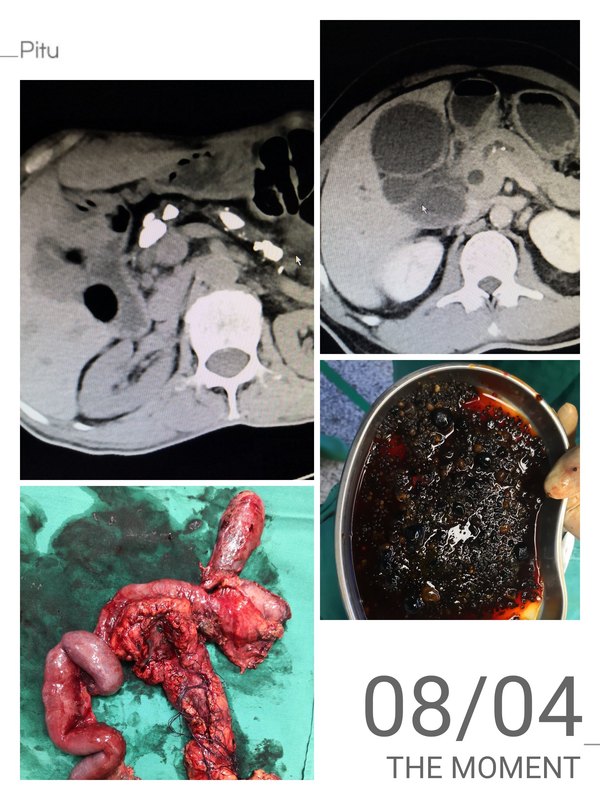

胰管結(jié)石應(yīng)早期治療

胰腺是人體重要器官,既有生成胰島素,控制血糖功能,又有分泌胰液,幫助消化的功能??傮w而言,胰管結(jié)石屬于少見疾病,國內(nèi)發(fā)病率約1%,部分病人沒有或很少有臨床癥狀,導(dǎo)致就醫(yī)時胰腺萎縮厲害,甚至合并發(fā)生了胰腺癌,故而需要明確其診治方案。 胰管結(jié)石病人主要有反復(fù)上腹痛,部位可以偏左或偏右,伴或不伴腰背部放射痛;少部分病人合并有糖尿病、脂肪瀉,甚至黃疸,具體根據(jù)結(jié)石部位,發(fā)病時間而定,主要依靠CT、磁共振檢查方能明確。 胰管結(jié)石一般分為四種類型,I型:結(jié)石主要位于胰頭部;II型:結(jié)石主要位于胰體部;III型:結(jié)石位于胰尾部;IV型:結(jié)石位于胰頭到胰尾部。治療方法依據(jù)不同分型而定。 近期我們連續(xù)收治了兩例胰管結(jié)石病人,均成功為其手術(shù)治療。第一例為65歲,因?yàn)樯细雇窗楸巢刻弁?個月由綿竹某醫(yī)院轉(zhuǎn)入,有糖尿病史7年,曾行胃穿孔修補(bǔ)術(shù)。我院FORCE CT檢查提示從胰頭鉤突到胰尾部均有粗大結(jié)石,胰管擴(kuò)張明顯。手術(shù)探查顯示胰頭部有一3*2厘米腫塊,切除后術(shù)中冰凍檢查查見癌細(xì)胞。因?yàn)橐认袤w尾部已經(jīng)重度萎縮,患者不得不接受全胰腺切除術(shù),分析其原因,系胰管結(jié)石導(dǎo)致了慢性胰腺炎,時間長了,逐漸癌變。術(shù)后需要終身胰島素替代治療,以控制血糖。第二例為56歲男性,因?yàn)槠つw鞏膜黃染2周入院,增強(qiáng)CT檢查提示胰管結(jié)石伴胰管擴(kuò)張,膽總管結(jié)石伴膽囊結(jié)石,磁共振檢查顯示主胰管擴(kuò)張,膽總管堆積泥沙樣結(jié)石,合并糖尿病10年。行胰管切開取石,胰頭部分切除,膽總管切除,胰腸吻合、膽腸吻合,手術(shù)中見其胰管直徑達(dá)到0.8厘米,膽總管膽囊內(nèi)堆積上千枚細(xì)沙粒樣結(jié)石,幸而術(shù)后病檢未見癌變。 胰管結(jié)石發(fā)病的具體原因并不清楚,但是慢性胰腺炎、胰腺纖維化導(dǎo)致胰腺外分泌功能紊亂是其重要原因,而結(jié)石的形成和胰管的堵塞,又可能加重胰腺的損害?,F(xiàn)代醫(yī)學(xué)僅僅能夠處理其并發(fā)癥,減輕對人體的損害,所以醫(yī)學(xué)并不完美,需要進(jìn)一步探索。取出結(jié)石,通暢胰腺的引流,往往能夠部分減輕胰管堵塞所導(dǎo)致的進(jìn)一步損害,甚至部分病例糖尿病可以減輕,所以及時科學(xué)處置尤其重要。